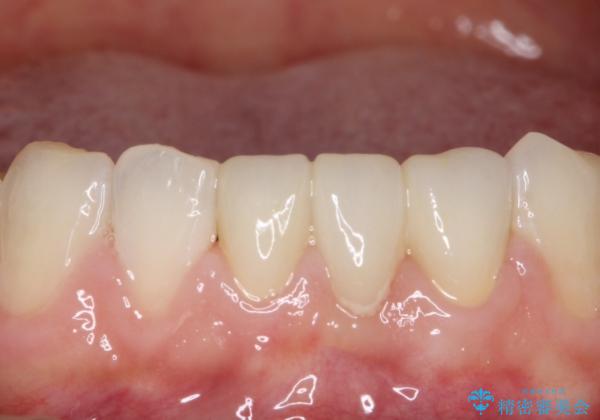

色調も周りの歯に合わせることができ、患者さんには満足していただきました。